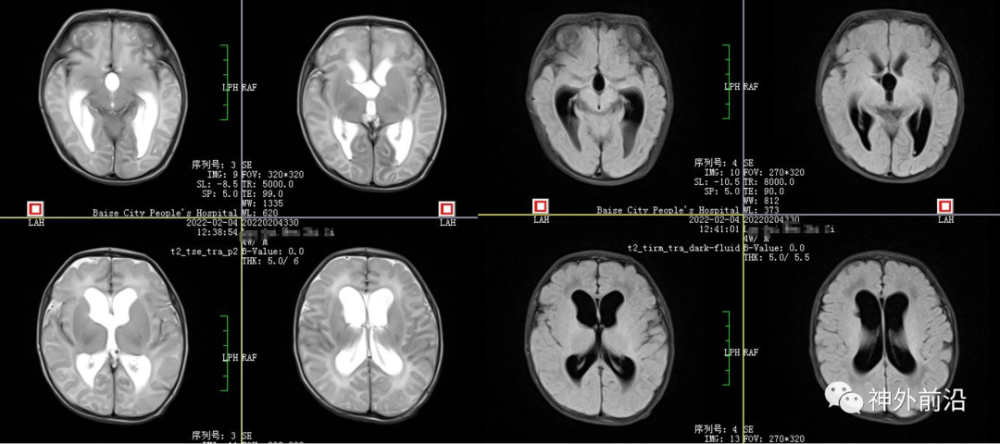

12.术后23天MRI

黄礼德:本例新生儿出院的时候是脑室系统稍大,术后我们反复性腰椎穿刺术,出院前颅内压力正常,目前没有脑积水。我们复查磁共振未见间质性水肿,但是该病例手术才两个月左右,后期还要进一步随访才行。